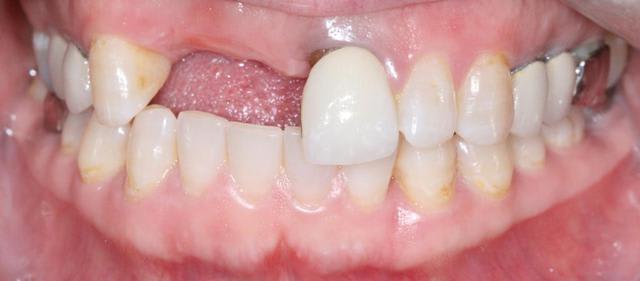

Bon ben j'ai implanté avant d'avoir refait la 21. Du coup j'ai mésialé la pose de 11 pour compenser la distalisation de 21.

Au final je n'ai pas fait de greffe osseuse... et j'ai réalisé une technique de rouleau sur 11-12 mais je reste un peu court à mon goût.

J'ai mis en place des transitoires sur 11-12-21 pour temporiser 3 mois pour voir la maturation des tissus mous.

Je réaliserai dans un second temps des piliers procera.

Je mets quelques photos de la patiente au cab et du prothèsiste d'Epinal.

La vraie difficulté a été de retrouver le milieu incisif pour déterminer la position des implants.

Les provisoires sont solidaires ? ( bravo pour le parallélisme)

Le zénith de la 21 doit être un peu plus distal pour que le résultat soit plus sympa

(comme tu l'as si bien fit sur la 11, allez quoi, un petit coup de bistouri et hop tu gagnes en esthétique)